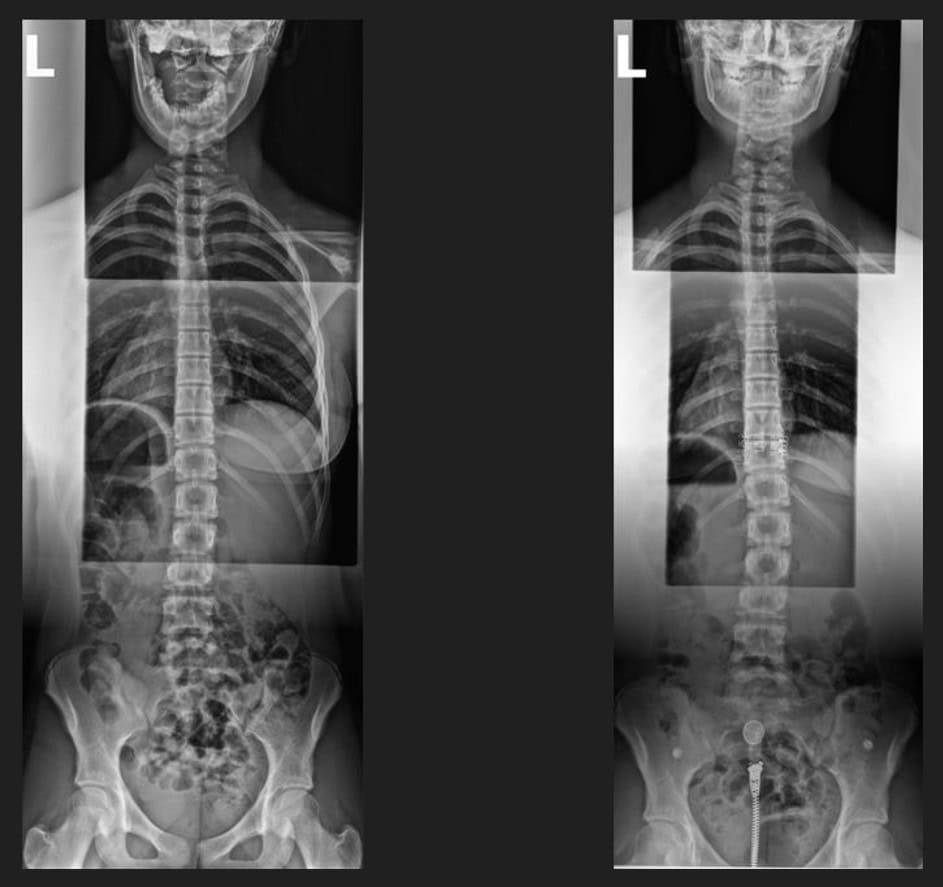

Pre & Post Scan